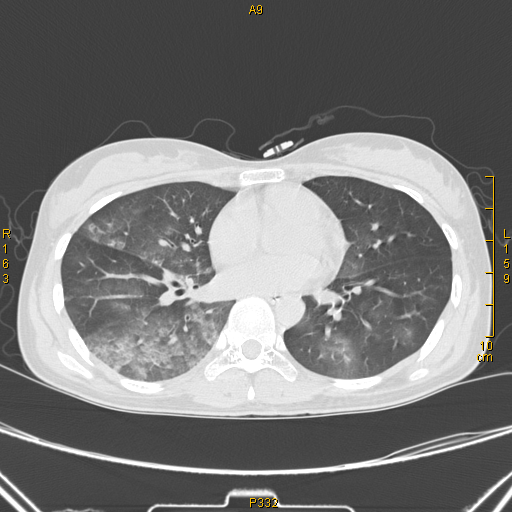

病例68——肺部典型病例(吸入性肺炎) - 医学影像学讨论版 - 爱爱医